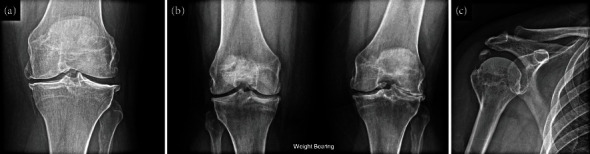

Abstract Image